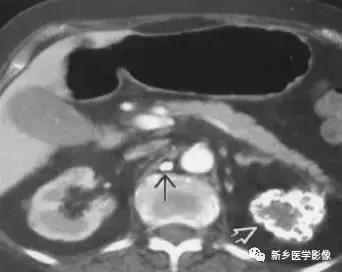

主要表现为点状的钙化,CT显示清晰,腹部平片有时候表现不明显。

19、肾上腺囊性病变

主要包括合并钙化的感染性病变及肿瘤性病变,如: 肾上腺囊肿,肾上腺癌,嗜铬细胞瘤。